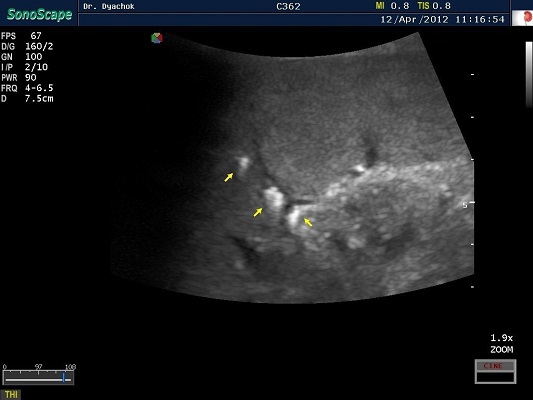

SonoScape S2N Vet – уникальная узи-система, выполненная в виде портативного ноутбука для легкой переноски. Отличается эта система цветным форматом визуализации, а также крайне чувствительными доплеровскими режимами, работающими на уровне премиальных аппаратов. При оптимальной цене – это очень хорошее и сбалансированное решение для ветеринарной клиники.

Диагональ монитора составляет 15,6 дюймов, что обеспечит комфортную работу для врачей и полный спектр визуализации для пациентов. Компактный вес не превышает 5 кг. (вместе с батареей), что оценят выездные бригады скорой помощи или ветеринары, выезжающие на дом.

• В, М, В/М, В/В, 4В, Тканевая гармоника, Пульсовая инверсная гармоника, Навигация биопсийной иглы (биопсийные направляющие), Режим улучшенной визуализации (подсветки) биопсийной иглы

• Изменение масштаба изображения в режимах реального времени и стоп-кадра

• Цветной, энергетический, направленный энергетический, направленный энергетический с высокимм пространственным разрешением, импульсно-волновой, постоянно-волновой доплер, тканевой доплер (опция)

• Дуплексный, триплексный режимы

• Трапецеидальное сканирование на линейных и конвексном датчиках

• Анатомический М-режим (опция), Цветной М-режим (опция), Панорамное сканирование (опция)

• Технология подавления спекл-шума MicroScan